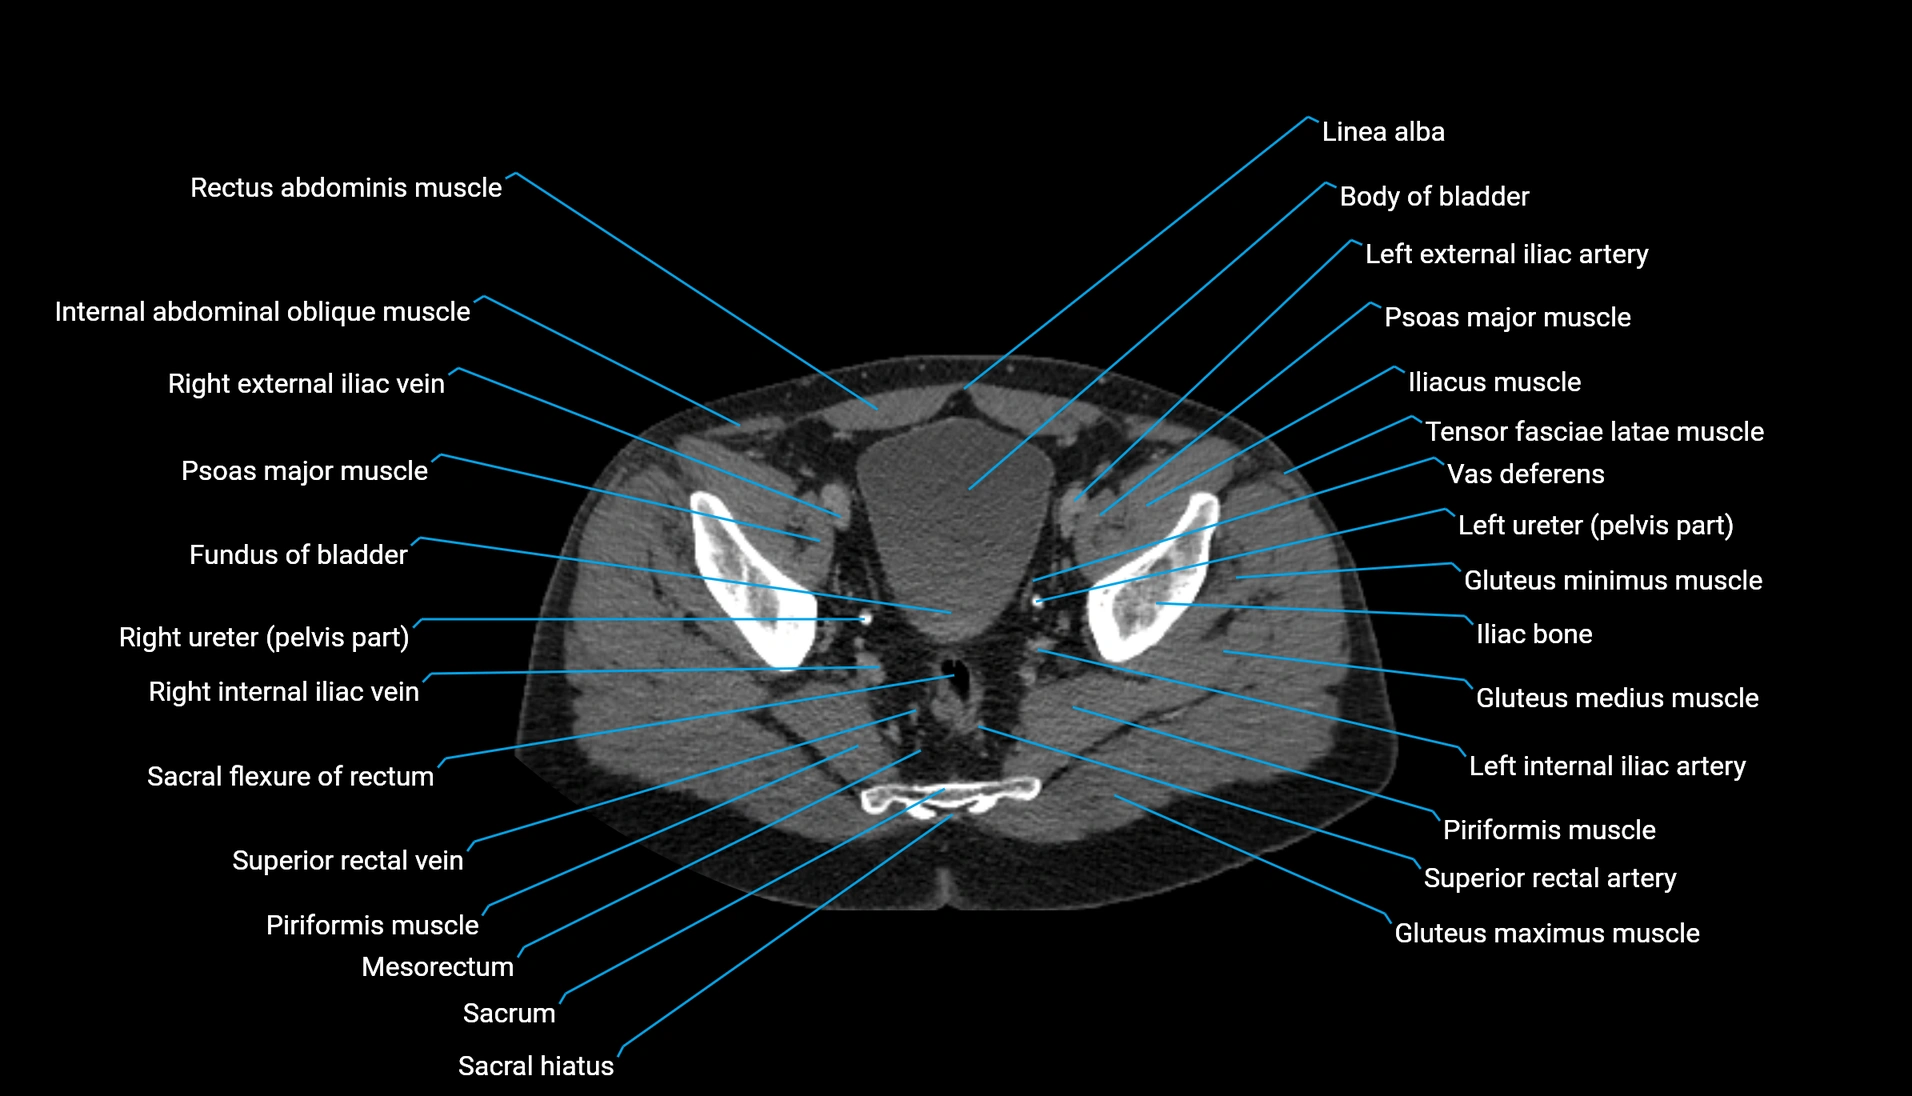

CT Appearance

Non-contrast CT:

-

Demonstrates cortical bone of acetabular rim in excellent detail

Detects fractures, dysplasia, retroversion, or bony overcoverage (pincer impingement)

3D reconstructions used in preoperative hip surgery planning

CT image